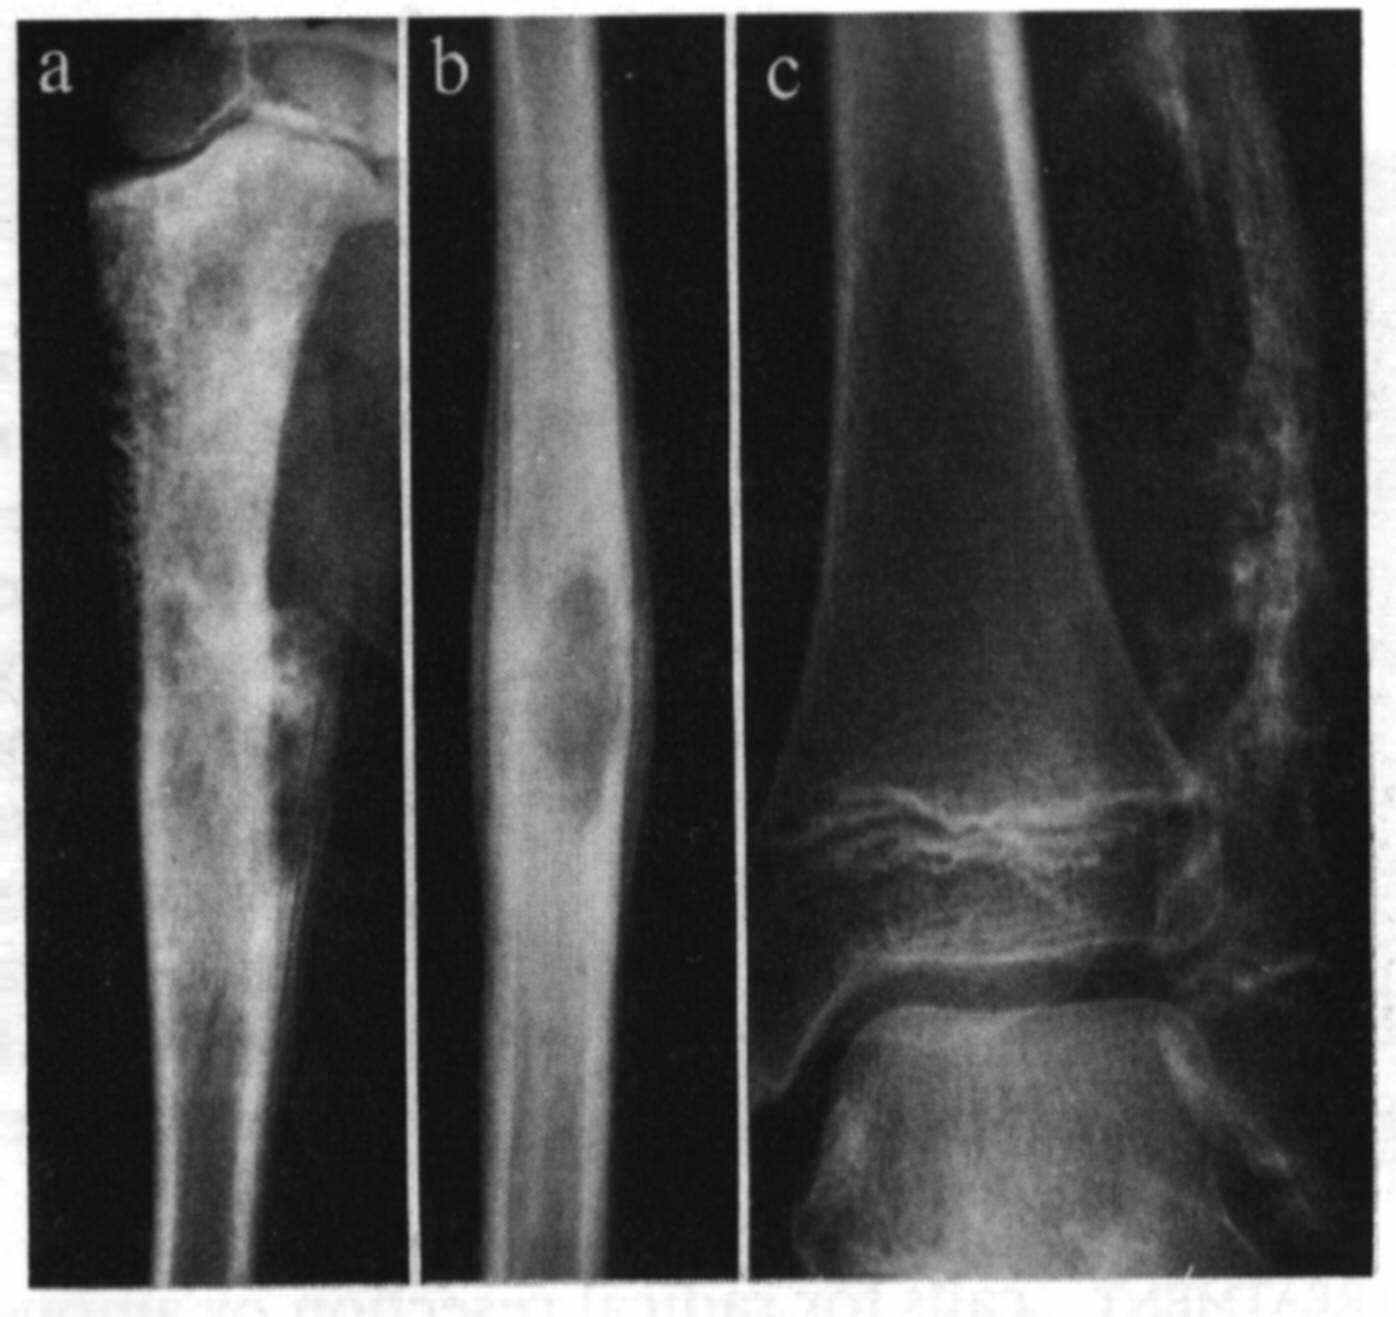

This is a benign tumor, which can have an aggressive process. It may also rarely metastasize to the lungs (<2%). Malignancy rates increase if there is local recurrence. This is more common in young females (20-50 years), and is uncommon in children with open physes.(19% of benign tumors). It usually occurs in the epiphysis or epimetaphysis of the long bones, with 50% occurring about the knee, with the vertebra, radius and sacrum in other cases. Multicentricity occurs in < 1% of patients. Pain is the usual symptom, referable to the involved joint, perhaps with mild swelling. Serum Calcium is usually normal.

Imaging

X-ray shows a purely lytic, destructive lesion eccentrically in the end of a long bone, mainly in the epiphysis, often extending up into the subchondral plate. The endosteal margin may be ill defined. The centre often has a soap bubble appearance, and the cortex is thinned and ballooned. In aggressive lesions, there may be soft tissue extension. To determine it’s behavior, CT, bone scanning and MRI scans are used, as well as distant systemic imaging.

A stage 1 tumor (Campanacci), is one which causes symptoms, appears latent radiographically, and has a benign histology. A stage 2 tumor, has a more aggressive radiological appearance, with no metastases, and a benign histology. A stage 3 tumor has a very aggressive X-ray, with soft tissue extension, but still a benign histology.